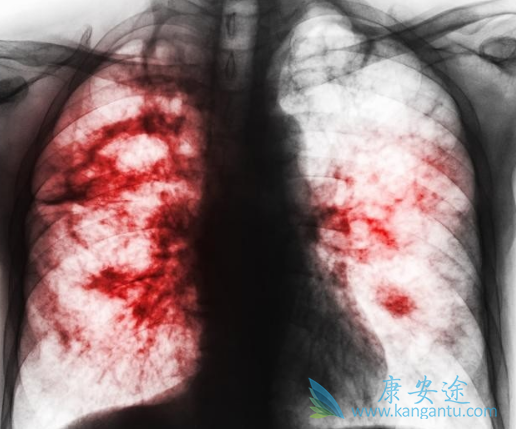

目前尚无针对特殊人群包括老年、儿童、孕妇或肝、肾功能不全患者的临床研究结果。对在不同年龄和性别等患者血药浓度资料分析结果显示患者的血药浓度不受年龄和性别等因素的影响,故不推荐根据年龄和性别调整凯美纳剂量。凯美纳的安全性评估是基于 312例晚期NSCLC患者的研究数据,常见不良反应为皮疹、腹泻和氨基转移酶升高,绝大多数为I~II级,一般见于服药后1-3周内,通常是可逆性的,无需特殊处理,可自行消失。